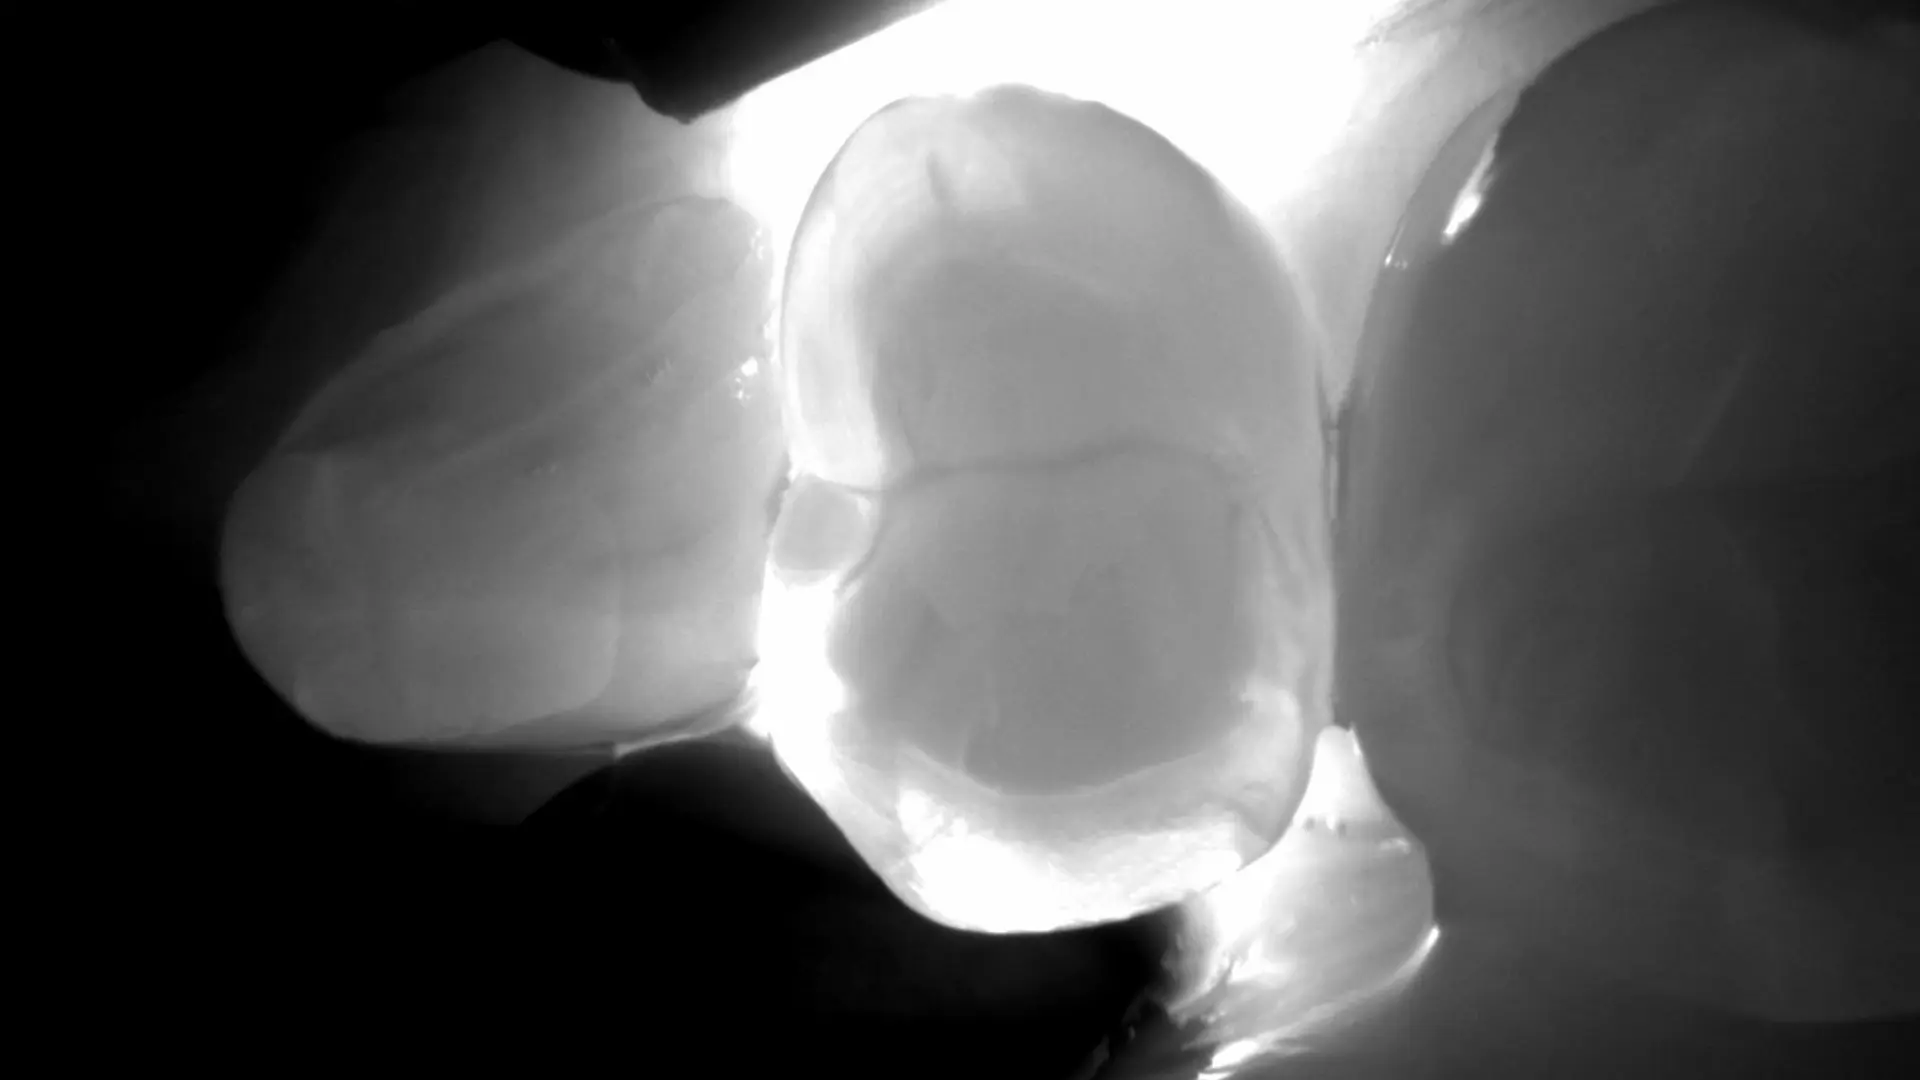

Tecnologia DIAGNOcam: diagnosi dentale senza radiazioni

L’evoluzione tecnologica sta trasformando il settore odontoiatrico, offrendo strumenti sempre più precisi ed efficaci per la diagnosi e il trattamento delle patologie dentali. Tra queste innovazioni, la DIAGNOcam si distingue come una soluzione all’avanguardia per la diagnosi precoce delle carie. Questo dispositivo utilizza la tecnologia DIFOTI (Digital Fiber Optic Transillumination), basata sulla transilluminazione con fibra ottica, che consente di individuare le lesioni cariose senza esporre i pazienti alle radiazioni ionizzanti.

La DIAGNOcam si avvale di fasci di luce laser a una lunghezza d’onda specifica di 780 nm, che attraversano il tessuto dentale. La luce viene assorbita o riflessa in modo diverso a seconda dello stato del dente: le aree sane risultano trasparenti, mentre le lesioni cariose bloccano il passaggio della luce. Questo crea immagini dettagliate che consentono al dentista di identificare carie e demineralizzazioni con grande precisione.

Questa tecnologia è particolarmente efficace per individuare carie occlusali e interprossimali, che possono sfuggire a un controllo visivo o ai metodi diagnostici tradizionali.

Le immagini fornite sono altamente dettagliate e permettono al dentista di analizzare le strutture dentali in profondità. Ciò migliora la precisione diagnostica rispetto ai metodi tradizionali.